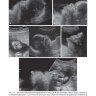

Примеры страниц из книги "Ультразвуковая дифференциальная диагностика в акушерстве и гинекологии" - Биссет Р.

Книга содержит информацию об анатомических особенностях строения, ультразвуковой визуализации матки, придатков, методиках сканирования, новейших технологиях при неизмененных состояниях, функциональных отклонениях, патологиях, выявляемых при мультипараметрическом УЗИ. Главы включают в себя обсуждение проблемных вопросов, практические советы и рекомендации, а также наиболее актуальные литературные источники.

Издание хорошо иллюстрировано. Большое количество схем, таблиц, рисунков, эхограмм позволяет более четко понимать визуальную картину многочисленных изменений, наиболее часто выявляемых при эхографии органов малого таза в клинической практике в норме и при патологии.